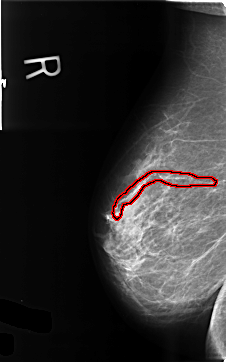

FILE: B_3435_1.RIGHT_MLO.OVERLAY

TOTAL_ABNORMALITIES 1

ABNORMALITY 1

LESION_TYPE CALCIFICATION TYPE VASCULAR DISTRIBUTION N/A

ASSESSMENT 2

SUBTLETY 5

PATHOLOGY BENIGN_WITHOUT_CALLBACK

TOTAL_OUTLINES 1

BOUNDARY